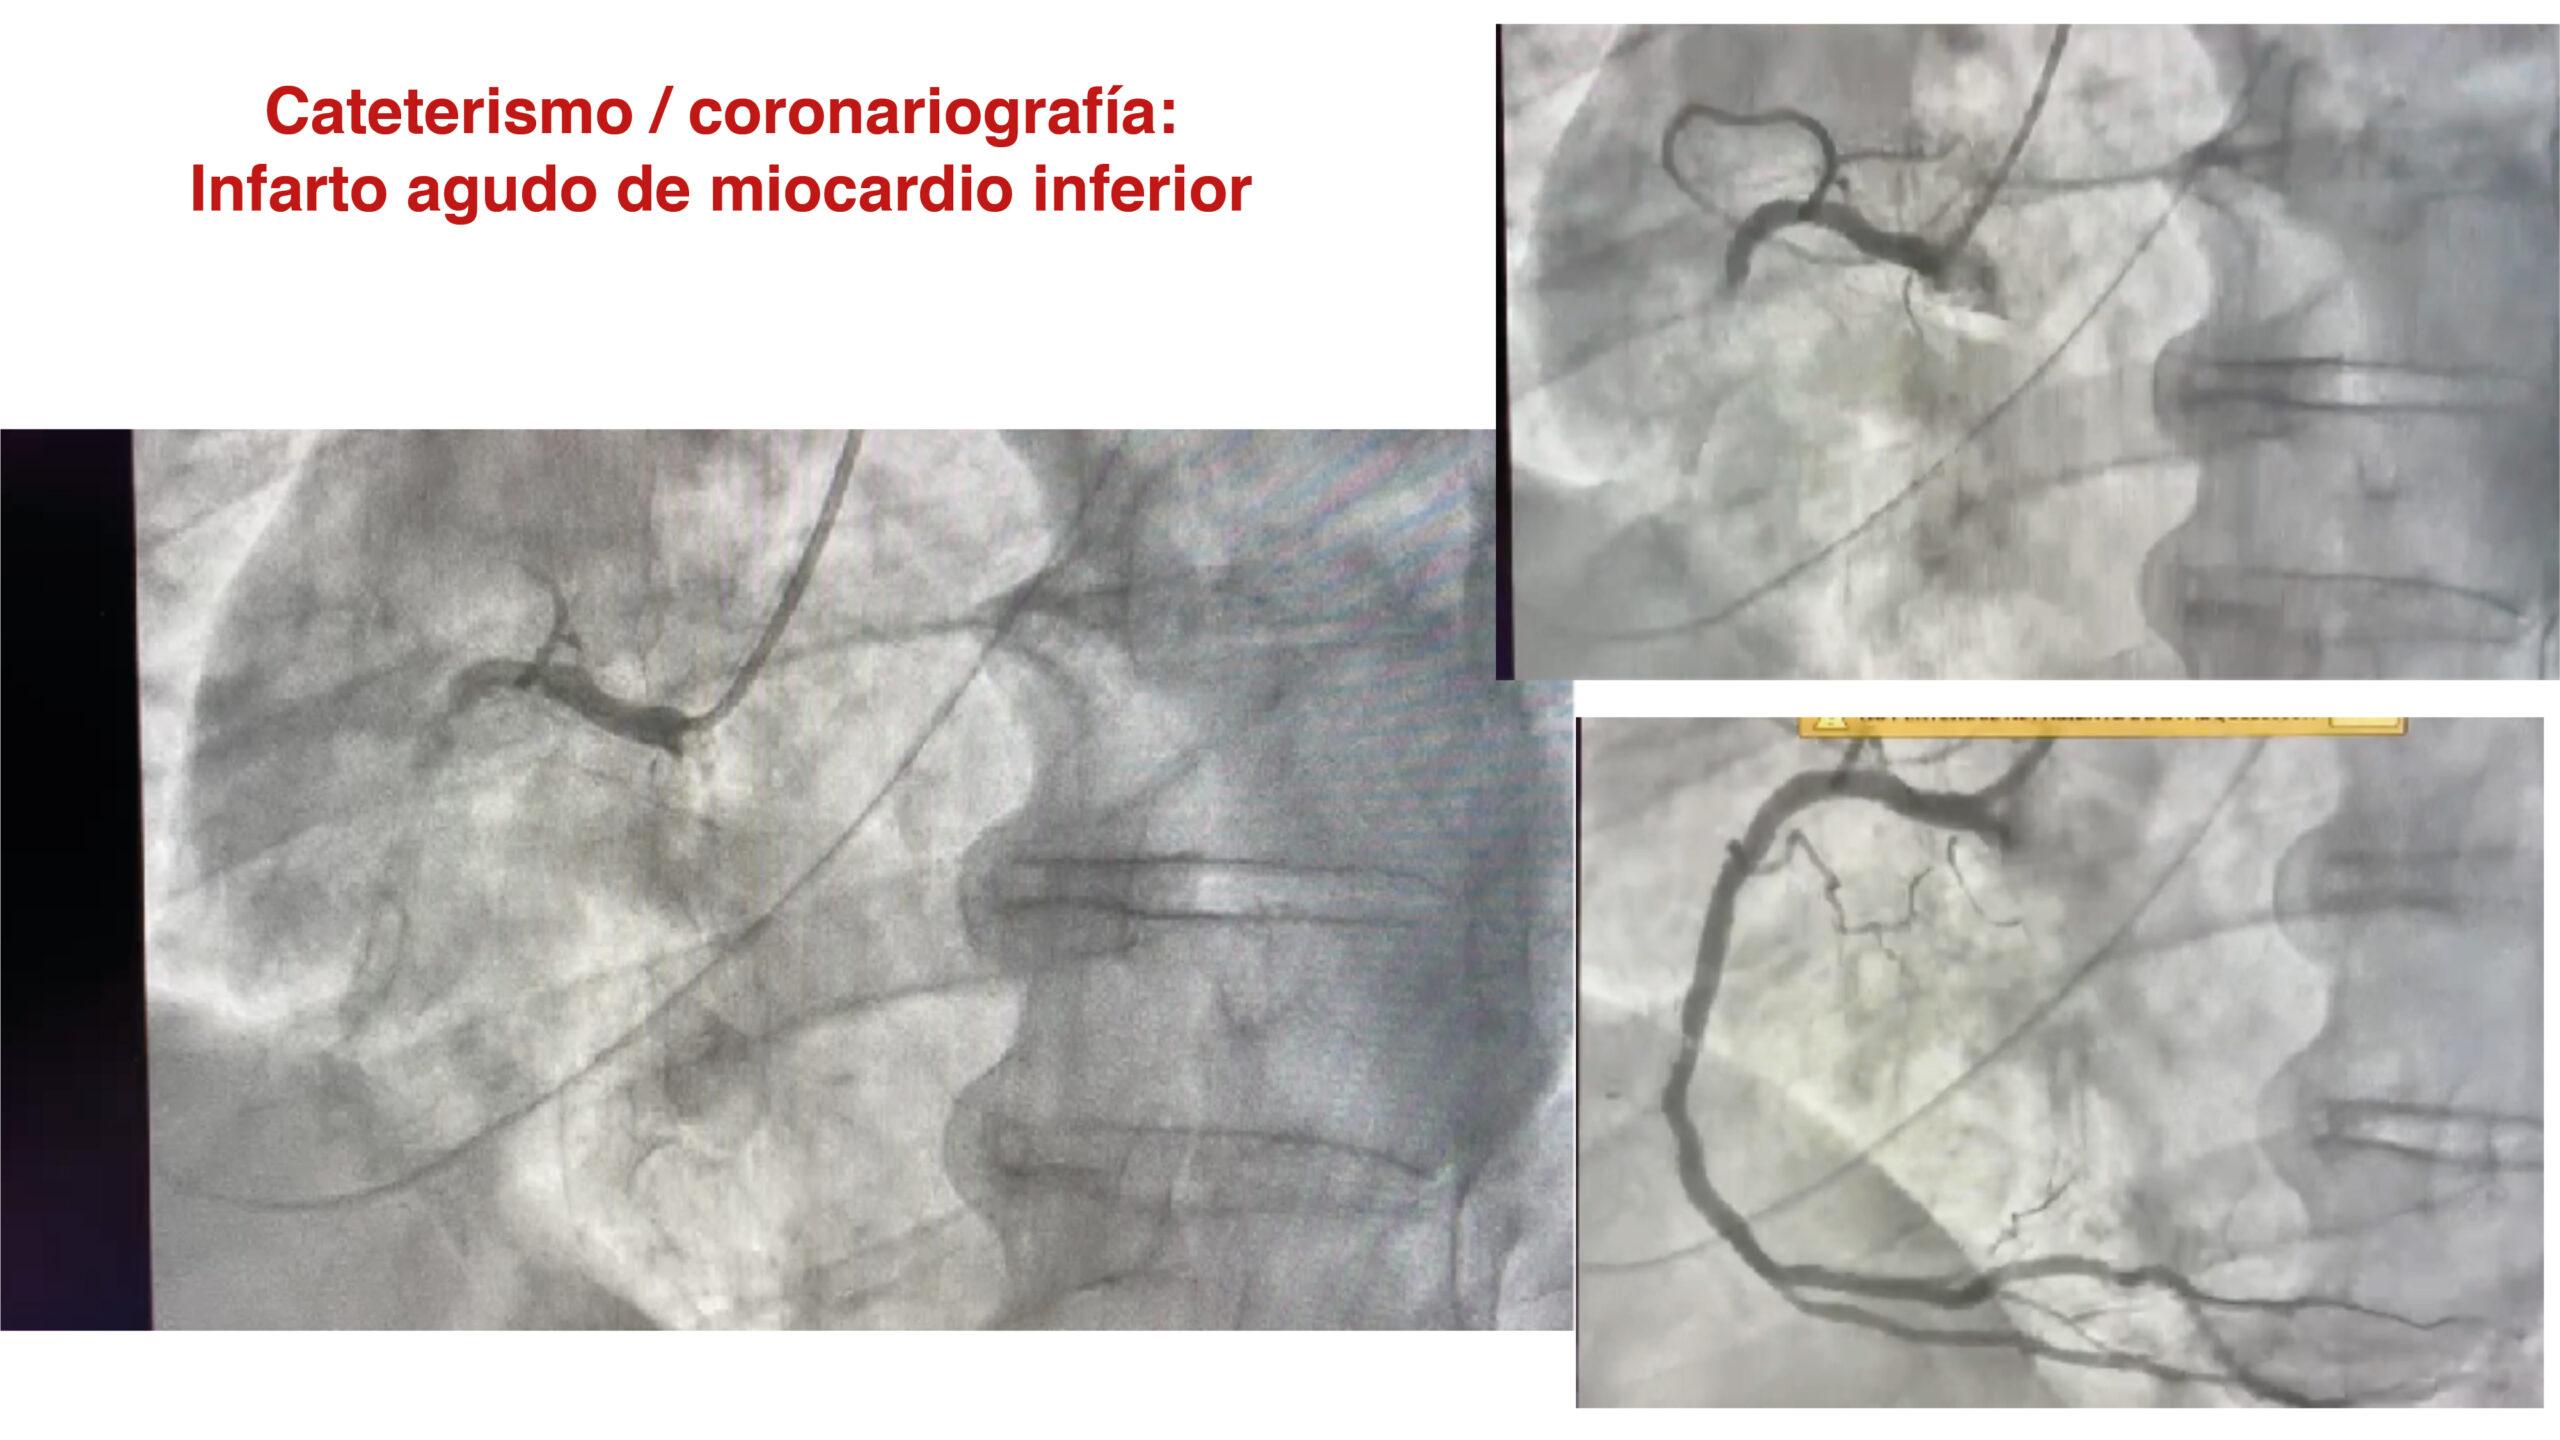

¿QUÉ ES EL CORAZÓN? ¿QUÉ ES UN INFARTO?